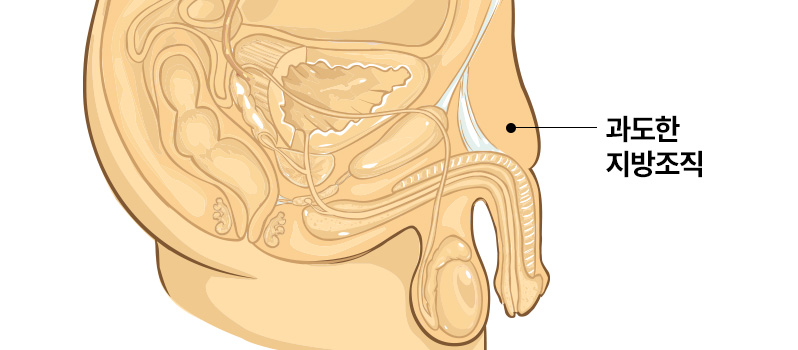

성기가 하복부 혹은

치골 주변의 지방조직에

파묻혀 길이가 짧아 보이는 경우

주된 원인이 하복부 및 치골주변의

과도한 지방조직에 의해 발생한 것인 만큼

지방흡입을 통해 길이연장의 효과를

기대해볼 수 있습니다